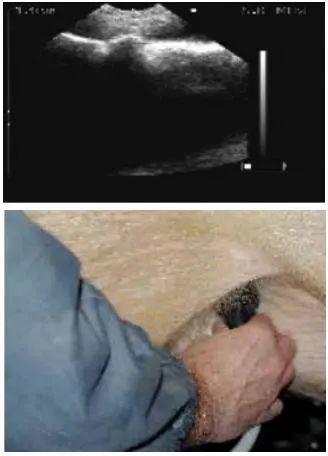

2.4 不同位置的扫描影像图

用B超进行妊娠鉴定时,应检测母猪身体的不同部位,以获得子宫内的详细情况,不同位置的扫描影像见图1、图2、图3、图4和图5。

图 4 位置4超声波影像图